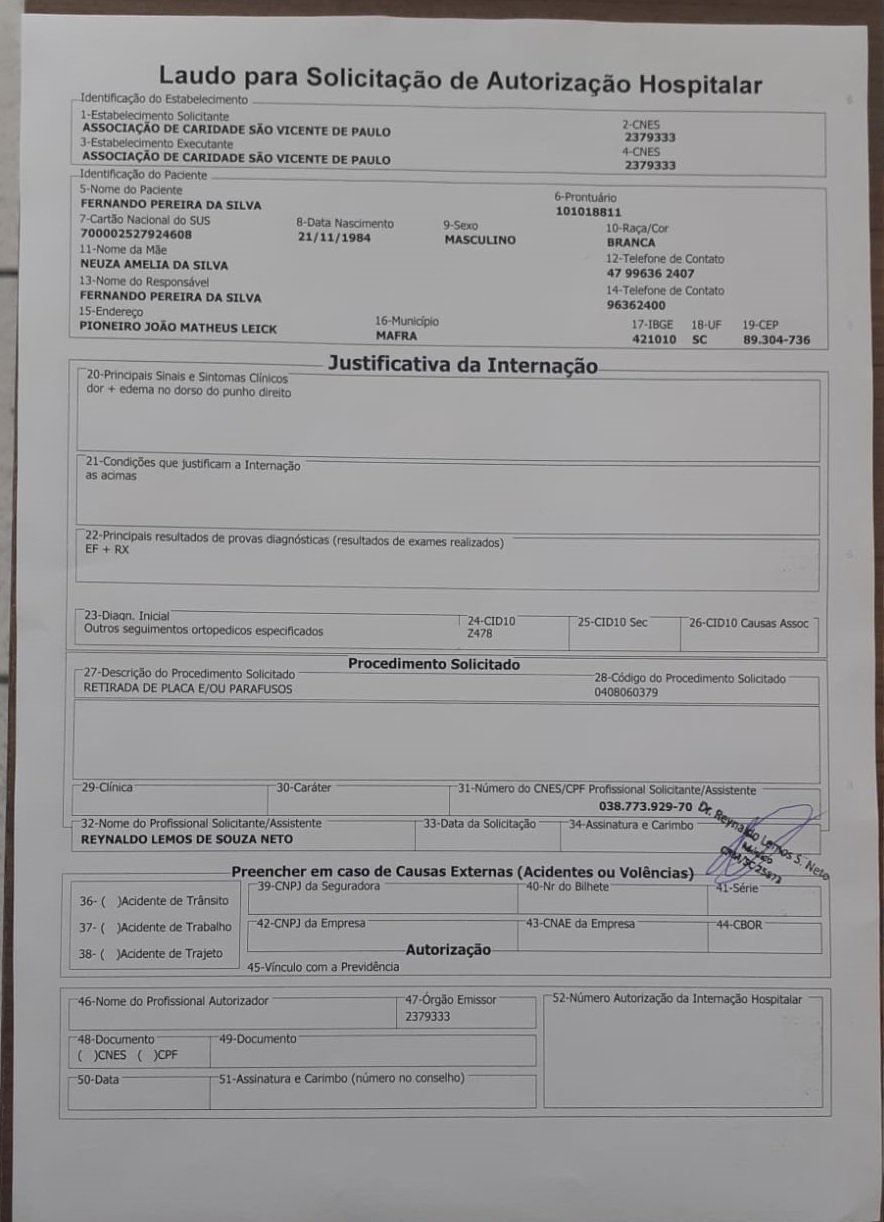

O mafrense Fernando Pereira da Silva precisa de ajuda para realizar uma importante cirurgia: Me chamo Fernando Pereira da Silva, tenho 38 anos sou morador da cidade de Mafra SC. A 2 anos fraturei meu braço (radio discal com extensão para metafise, fratura grave com cominuicao e perca óssea) passei por cirurgia onde foi colocado uma placa e 7 parafusos. Ao longo do tempo apareceu um cisto no carpo ( parte de cima da mao ) após vários exames foi constatado que 2 dos parafusos está transfixado no tendão, onde está causando infecção e atrofiando 3 dedos. Na última consulta foi feito uma solicitação cirúrgica para a retirada dos parafusos que estão causando a infecção e o atrofiamento dos dedos. A liberação da cirurgia pelo SUS demora em média 2 anos. Preciso realizar essa cirurgia o quanto antes para não perder o movimento dos dedos. Peço encarecidamente a ajuda para poder realizar a cirurgia. “A sua doação fará toda a diferença. Por favor, contribua com o que puder e ajude-nos a atingir nossa meta. Compartilhe esta vaquinha com seus amigos e familiares e junte-se a nós nesta causa importante. Juntos, podemos fazer a diferença!”